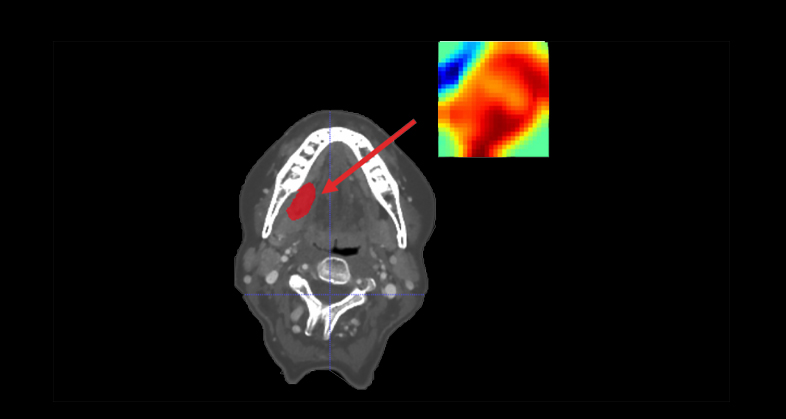

Oncology

CT-based clinical-radiomics model to predict progression and drive clinical applicability in locally advanced head and neck cancer